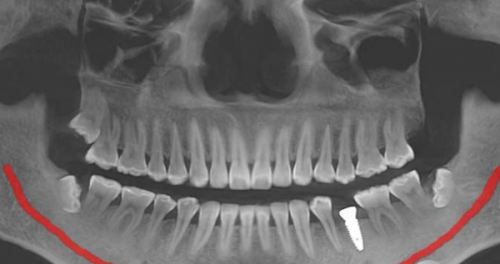

在进行种植牙手术之前,口腔检查是必不可少的一步。医生会对你的口腔进行全方面检查,包括牙齿状况、牙周组织、颌骨状况等。这就像是盖房子前要先考察地基一样,只有确定你的口腔有足够的骨量和软组织来支持种植牙,手术才能顺利进行。比如,如果你的牙槽骨骨量不足,可能就需要精良行骨增量手术。

接着,医生会根据你的口腔状况和种植需求,为你制定个体化的种植方案。现在的技术特别精良,会涉及数据采集、三维模型重建等手段,这样能精细地确定种植牙的位置、方向和深度,达到至佳成效。就好比给你量身定制一套合适的衣服,让种植牙和你的口腔理想适配。